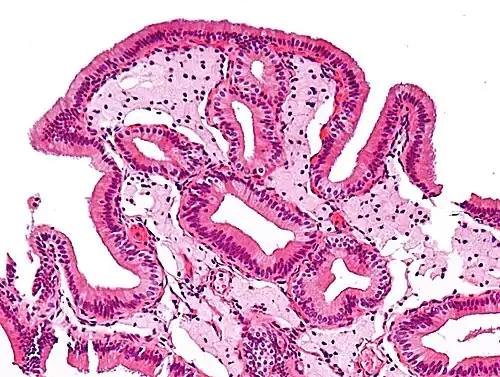

Micrograph of cholesterolosis of the gallbladder

The name strawberry gallbladder comes from the typically stippled appearance of the mucosal surface on gross examination, which resembles a strawberry. The term was coined by surgical pathologist William C. MacCarty of the Mayo Clinic in 1910.[2] Cholesterolosis results from abnormal deposits of cholesterol esters in macrophages within the lamina propria (foam cells) and in mucosal epithelium. The gallbladder may be affected in a patchy localized form or in a diffuse form. The diffuse form macroscopically appears as a bright red mucosa with yellow mottling (due to lipid), hence the term strawberry gallbladder. It is not tied to cholelithiasis (gallstones) or cholecystitis (inflammation of the gallbladder).[3]